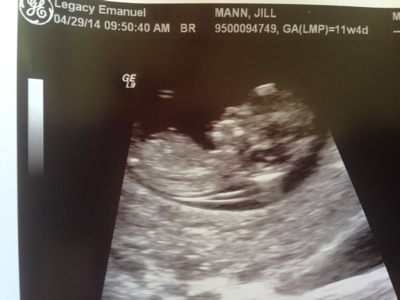

Hello! I'm new to this forum but I'd love to hear what you guess from our 12 week 0 day ultrasound. I really appreciate you taking the time to guess. Skull and Nub guesses would be great! Thanks so much!